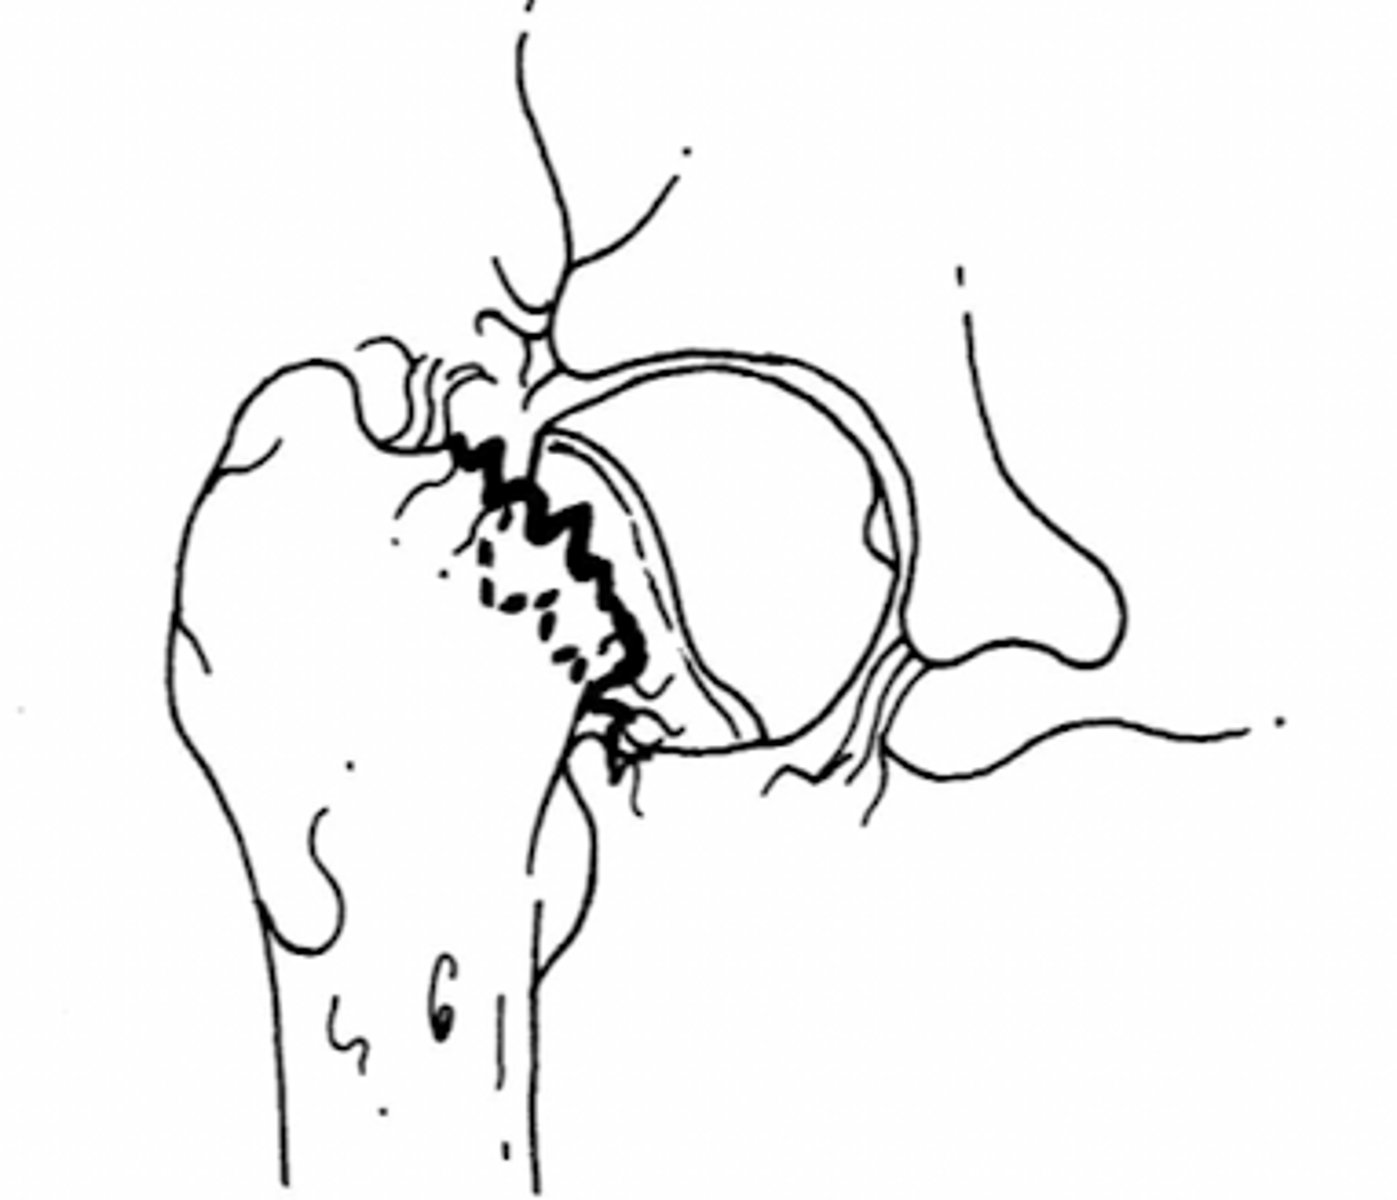

subtrochanteric fx

subtrochanteric fx